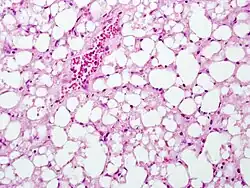

The second phase occurs between 24 hours and 72 hours following overdose and consists of signs of increasing liver damage. In general, damage occurs in liver cells as they metabolize the paracetamol. Hallmark pathology on liver biopsy includes regions of coagulative necrosis in zone 3 of the liver acinus, around the central venules, as these hepatocytes have higher concentrations of cytochrome P450 enzymes compared to zone 1 hepatocytes surrounding the portal venule of the acinus. Remaining viable hepatocytes frequently show ballooning injury and steatosis.[13] The individual may experience right upper quadrant abdominal pain. The increasing liver damage also changes biochemical markers of liver function; International normalized ratio (INR) and the liver transaminases ALT and AST rise to abnormal levels.[14] Acute kidney failure may also occur during this phase, typically caused by either hepatorenal syndrome or multiple organ dysfunction syndrome. In some cases, acute kidney failure may be the primary clinical manifestation of toxicity. In these cases, it has been suggested that the toxic metabolite is produced more in the kidneys than in the liver.[15]